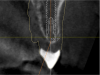

Fig. 19 through Fig. 24 The radiographic guide in place (19); the CBCT scan was taken with the guide seated in the mouth (20); after planning and milling the drill guide was inserted (21), guide in mouth with key and 2-mm bur (handpiece removed for photograph, 22), postoperative x-ray (23), immediate postoperative photograph of healing abutment (24). Surgery was done through tissue punch.